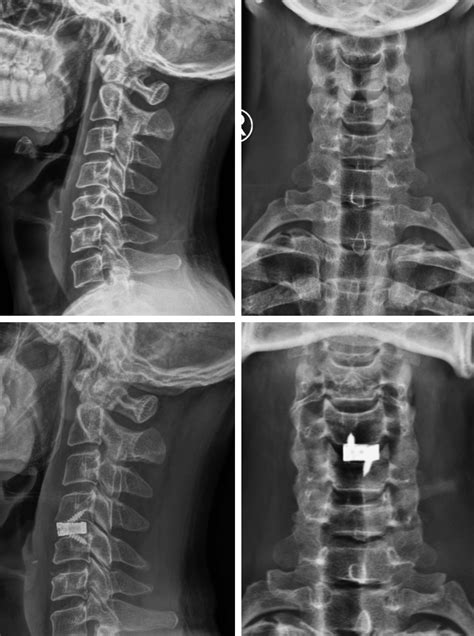

To grasp the concept of a Disc Osteophyte Complex, it is helpful to look at the individual components that form this structure. The spinal column consists of vertebrae separated by intervertebral discs, which act as shock absorbers. Over time, these discs can become dehydrated and lose their structural integrity, leading to a bulge or herniation. Simultaneously, the body attempts to stabilize the segment by developing bony growths at the edges of the vertebrae, known as osteophytes or bone spurs.

When these two issues—the disc protrusion and the bone spurs—merge at the same spinal level, they form a mass that can protrude into the spinal canal or the neural foramina (the openings where nerves exit). This combination creates a Disc Osteophyte Complex, which significantly increases the likelihood of nerve compression compared to either condition occurring in isolation.

In cases where conservative treatments fail to provide adequate relief, or if there is evidence of progressive neurological decline, surgical intervention may be considered. Surgeons aim to decompress the nerves affected by the Disc Osteophyte Complex. Common procedures include:

• Discectomy: Removing the portion of the disc that is pressing on the nerve.

• Laminectomy: Removing a small portion of the bone to create more space in the spinal canal.

• Spinal Fusion: In cases of significant instability, the surgeon may fuse the affected vertebrae together using bone grafts and hardware.